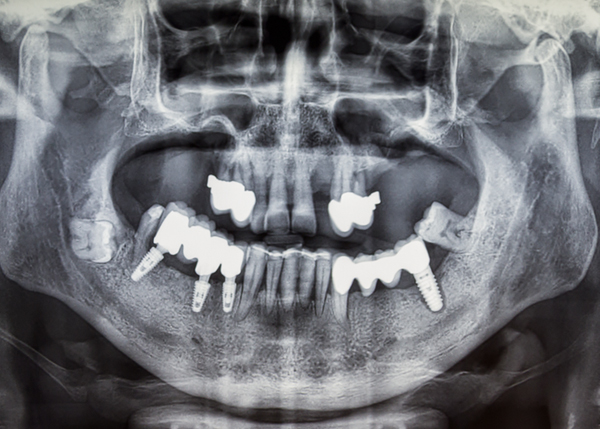

신뢰할 수 있는 선택, 실제 치료 사례들 입니다.

일반 케이스 부터 고난이도 케이스까지

수많은 성공적인 임플란트 케이스로 입증된 전문성